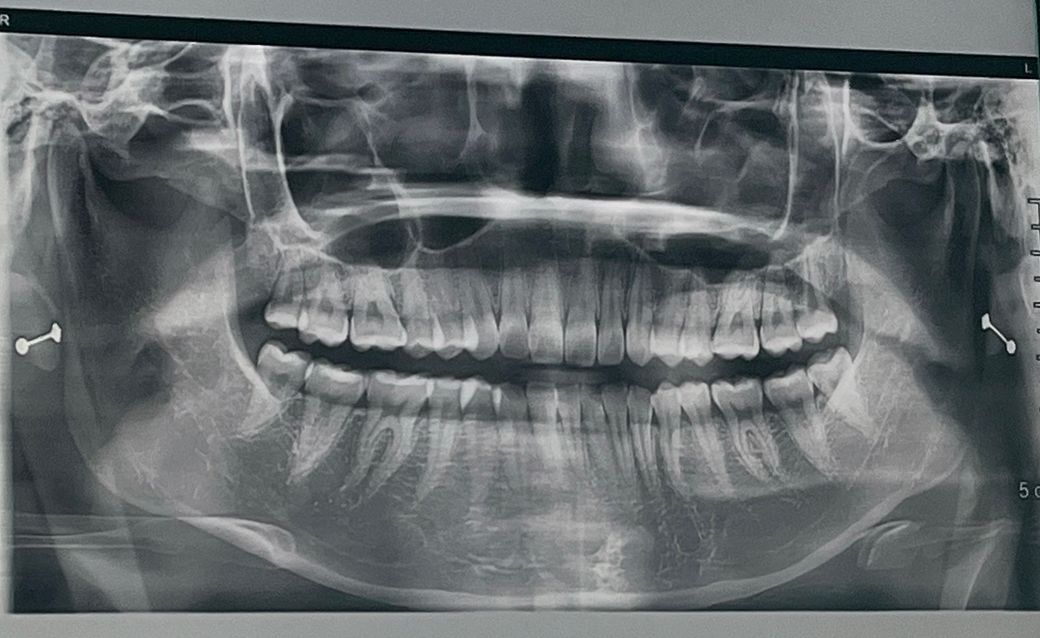

턱관절 엑스레이 제발 한번만 봐주세요...ㅠㅠ

1. 양쪽 턱관절 마모되었나요? (양쪽 상태가 궁금해요)

3. 디스크가 빠졌는지 턱관절은 어때보이나요?

4. 엑스레이상 충치는 있어보이나요?

5. 사랑니 4개가 모두 났는데 엑스레이상 발치를 해야할것같나요?

• 2번 째 사진

1. 양쪽 턱관절 다 마모는 눈에 띄지 않습니다

3. 정상입니다

4. 파노라마 사진에서는 충치 정밀하게 판독 안합니다 눈에띄게 큰 충치는 없습니다

5. 사랑니 4개 모두 발치 불필요합니다 아주 바르게 잘 났습니다 관리만 잘해주세요

사랑니는 모두다 똑바로 맹출되서 관리가 잘되면 발치를 안하셔도 될것같습니다. 턱관절은 파노라마 상으로는 정확히 볼수 없고 대학병원에 가셔서 턱관절 CT를 찍어보시는게 좋을것같습니다 .